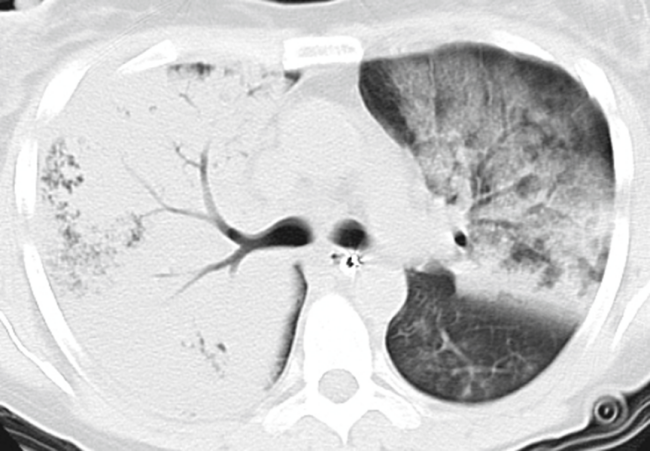

三、教学内容及课堂设计 (一)讲授内容: 1.课时总体分配 第一节 胸部的体表标志 10分钟 第二节 胸壁、胸廓与乳房 10分钟 第三节 肺和胸膜检查 140分钟 第四节 呼吸系统常见疾病的主要症状和体征 40分钟 【教学设计和要点】 1.导课:给一个COPD患者看“八字”(患者存在肺气肿,现在走路比同龄人慢,曾经因为气胸住过院)(1min) 2.前测:复习胸部解剖结构,提出胸部体格检查的意义;用临床病例说明胸部体格检查的条件要求。(2min) 3.用既往师兄师姐体格检查中在SP和患者胸部不停的触摸,提出体表标志的意义;(7min) 骨骼标志:在图片的基础上添加动画,标识出部位,并讨论临床意义 垂直线:在图片的基础上,添加垂直线,讲解意义 自然陷窝和解剖区域:在图片的基础上添加动画,标识出部位,并讨论临床意义 肺和胸膜界限:结合解剖特点,分析解剖与临床的关系;各类疾病体格检查中可能出现的异常体征,为后续检查做好铺垫。 4.胸壁胸廓和乳房 (1)胸壁(2min) 静脉:如何检查及意义(使用肺癌患者上腔静脉阻塞综合征,并为后续体格检查做好铺垫) 皮下气肿:如何检查,临床上一个气胸患者突发气促加重,体格检查如何发现,也为后面气胸体格检查做好铺垫。 胸部压痛:压痛检查方法,压痛部位与疾病,并与前面体表标志相结合,复习前面的内容。 肋间隙:结合前面体表标志,结合导课的COPD患者。 (2)胸廓(2min) 正常胸廓和异常胸廓:用图片展示,并说明异常胸廓对身体的影响 异常胸廓的意义:结合临床案例讲解 (3)乳房(6min) 正常乳房和体检方法:用案例讲解乳房检查的注意事项 视诊:对称性;皮肤改变;乳头;腋窝和锁骨上窝 触诊:触诊顺序;触诊方法;触诊异常;包块的触诊(复习淋巴结触诊内容,并强调乳房淋巴结触诊的意义) 常见乳腺疾病的体格检查:用初产妇急性乳腺炎案例;晚期乳腺癌患者图片;肝硬化患者乳腺增生(为后续肝硬化患者就诊做好铺垫,同时复习胸壁胸廓检查) 4.肺和胸膜 结合南北差异,季节差异讲解肺和胸膜体格检查的条件要求。(2min) (1)视诊 呼吸运动:使用演示技巧,说明呼吸运动影响因素、构成和意义;同时为呼吸频率的检查做好铺垫(6min) 呼吸频率:检查方法(结合呼吸运动的模拟,让学生理解检查方法和注意事项);异常的临床意义(6min) 呼吸节律:模拟呼吸节律变化,结合临床案例讲解其临床意义(6min) (2)触诊 胸廓扩张度:与同学一起呼吸,分析检查方法注意事项,分析异常的意义(6min) 语音震颤:123和1234方法;通过临床病例解释临床意义(6min) 胸膜摩擦感:用衣服摩擦的动作说明胸膜摩擦感产生机制和检查方法。(6min) 小结视诊和触诊内容(2min) (3)叩诊 叩诊方法:复习基本检查方法(4min) 叩诊音影响因素:带领同学们叩诊桌面,要求同学们叩出桌面下的固定钢条边缘(3min) 肺部叩诊音分类和肺部正常叩诊音:结合同学们的叩诊体验,使用表格比较不同肺部叩诊音的分布及原因。(3min) 肺界的叩诊:肺上界、前界、下界(6min) 肺下界移动度:结合同学们呼吸,解释肺下界移动度的影响因素;结合叩诊方法,说明肺下界移动度检查方法。(6min) 侧卧位叩诊:结合部分患者不能坐位,引出侧卧位叩诊的必要性,再解读侧卧位叩诊的异常情况。(6min) 胸部异常叩诊音:结合临床病例讲解(12min) (4)听诊 听诊方法:复习体格检查基本方法,强调听诊的注意事项,强调实事求是。(2min) 正常呼吸音:图片中增加链接,播放对应呼吸音。(8min) 异常呼吸音:图片中增加链接,播放对应呼吸音。解释对应的机制和临床意义。(10min) 湿啰音:模拟湿啰音,解释原因,复习咳嗽咳痰时相关内容。(6min) 对湿啰音分类,讲解其分类方法及临床意义。(10min) 干啰音:与湿啰音比较其音色的不同,与学生讨论干啰音产生机制。(6min) 分析干啰音的分类,讲解其临床意义(6min) 语音共振:复习语音震颤,告知学生两者不同及相关性;复习语音震颤的检查方法,支出语音共振的检查方法。(3min) 胸膜摩擦音:复习胸膜摩擦感的检查方法和临床意义,讨论胸膜摩擦音的检查方法和临床意义。(3min) (5)肺部体格检查的顺序和方法(2min) 使用表格的方式讲解,结合图片和链接并听诊内容进行小结。(4min) 5.常见肺部疾病的体征 利用常见肺部疾病的体征,联系病理改变,回顾前面所学习相关内容,加强病理与临床的联系。 强调所有疾病的体征均按照视触叩听的顺序汇报。(1min) (1)大叶性肺炎:准备一张大叶性肺炎CT片,右肺是实变期,左肺为消散期,讨论病理改变,分析其为什么不同时期出现不同体征。(8min)